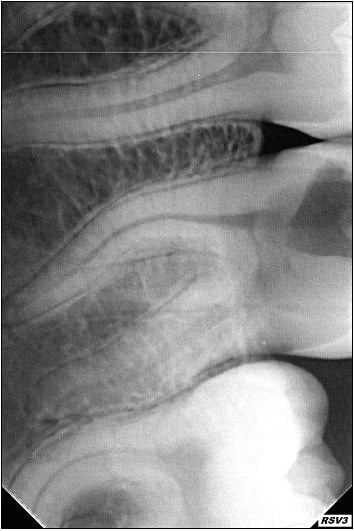

Petite endo bizarre...

Endo 17  2  c nes xyk9ig - Eugenol

Endo 17  3  postop iprbqy - Eugenol

Endo 17  1  preop n6m5ub - Eugenol

très propre